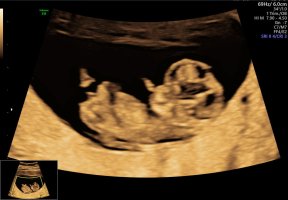

Ultralydbilder ✨